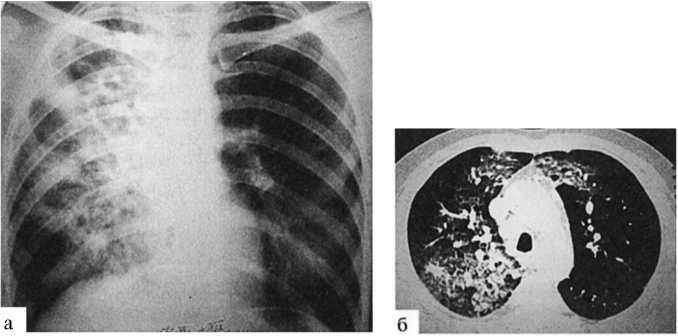

- Основные рентгенологические признаки казеозной пневмонии:

- протяжённость поражения — от одной доли (3-5 сегментов) до всего лёгкого.

- Затемнение — высокая интенсивность тени, сначала однородная, затем становится неоднородной с множественными просветлениями за счёт распада.

- Деструкции — множественные полости распада, иногда достигающие более 4 см в диаметре (гигантские каверны).

- Средостение — смещается в сторону поражения, отмечается сужение межрёберных промежутков и высокое стояние купола диафрагмы.

- Бронхогенное обсеменение — очаги инфильтрации в нижних отделах поражённого лёгкого и противоположном лёгком[2][7].

При лобарной казеозной пневмонии на рентгенограмме видно обширное затемнение всей или большей части доли лёгкого. Первоначально оно однородное, но со временем появляются участки просветления неправильной формы. В дальнейшем формируются острые туберкулёзные каверны. При лобулярной казеозной пневмонии на снимках определяются крупные тени неправильной формы с нечёткими контурами, часто симметрично в обоих лёгких. При томография выявляются множественные полости распада[3].

В более чем 50 % случаев изменения двусторонние, выраженные массивными затемнениями верхних долей с деструкциями и бронхогенным обсеменением нижних отделов[2].

- На компьютерной томографии в уплотнённой доле лёгкого отчётливо видны расширенные бронхи, заполненные воздухом. Из-за потери эластичности поражённая доля уменьшается в размере[3].